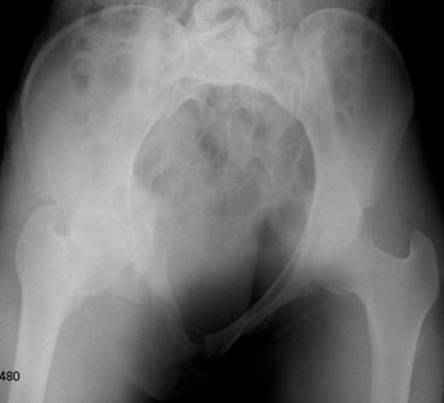

Серия до- и послеоперационных снимков этой пациентки. Хотя бы post factum обсудить. Не знаю, что можно сделать с задними отделами стержневым аппаратом, но три крепких парня открытым путем с помощью "волшебных" слов еле-еле смогли отрепонировать - сзади все было очень ригидно!